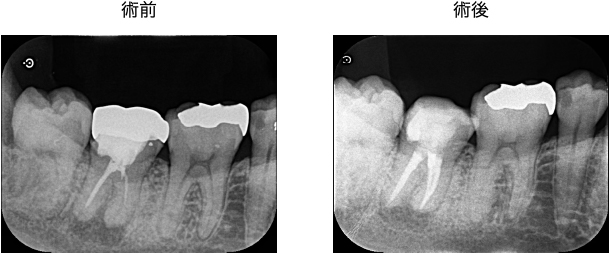

過去に根管治療を受けており、根の先に膿がたまり骨吸収が起こっている、根尖性歯周炎を発症している状態でした。ただ、根の先の病変の大きさはそこまで大きくはなく、現在の根管治療自体も不十分である点、虫歯による感染が疑われる点から、再根管治療により治癒する可能性は十分にある状態でした。

まずは古い銀歯を除去し、中で隠れていた虫歯を徹底除去しました。その後、ラバーダムを装着し、根管拡大形成・根管充填を行いました。残存歯質が比較的十分残っていたため、根の先の病変さえ治癒してくれれば、長期的にしっかりと残せる可能性が高い状態でした。このまま12ヶ月の経過観察となりました。

根管治療後12ヶ月のCT画像にて、はっきりと骨の回復・再生が認められました。患者様の「噛むと痛い」という症状も消失し、経過良好といえます。最終的には、ジルコニアクラウンを装着し、治療は終了となります。